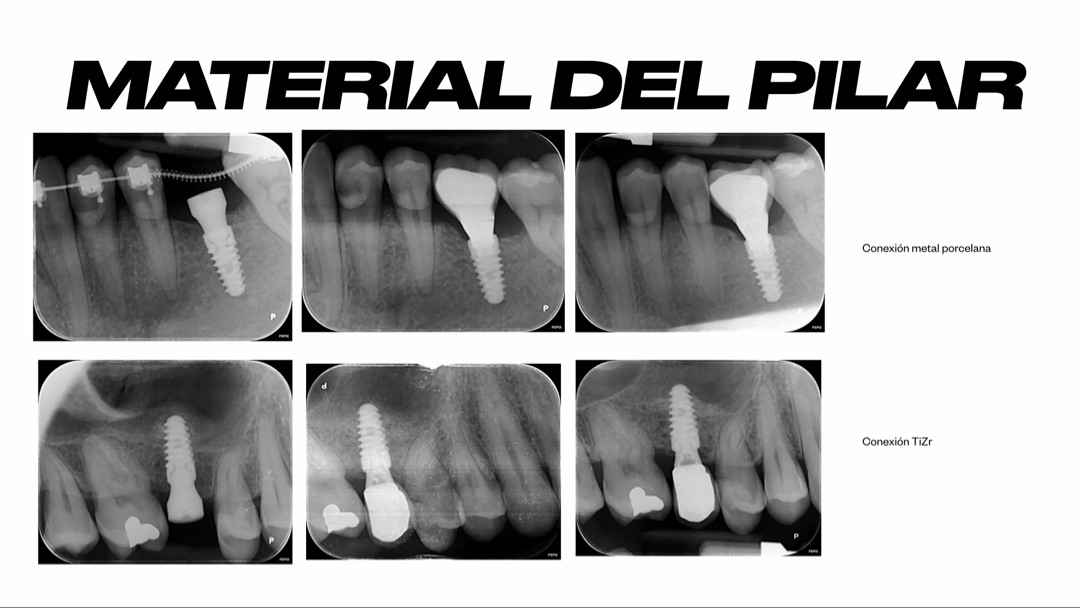

Vamos a hablar de la parte “invisible” del implante: la conexión.

Simplificando mucho:

- Plataforma externa: conexión más antigua, la unión prótesis–implante queda más “expuesta”.

- Plataforma interna: la conexión va más protegida dentro del implante.

Dentro de las plataformas internas, hay un tipo de conexión que para mí marca un antes y un después: la conexión cónica.

Es la que yo utilizo en Smilelife.

¿Por qué?

- Ofrece mayor estabilidad mecánica entre implante y pilar.

- Genera un sellado más preciso, con un microespacio mínimo.

- Ayuda a reducir micromovimientos y filtraciones bacterianas en esa zona tan crítica.

¿La parte “negativa”? Que no es el sistema más sencillo de manejar. Requiere algo más de destreza al colocar y al rehabilitar. Pero, precisamente por eso, para mí es el gold standard cuando pienso en estabilidad y salud a largo plazo.